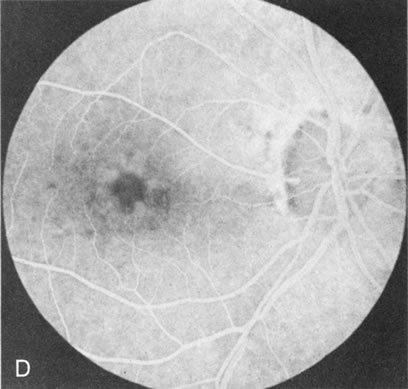

In retinitis pigmentosa (RP), the pigment abnormalities of atrophy, migration, and clumping are made apparent by transmitted hyperfluorescence and blocked hypofluorescence (Fig. 1A). Patients who have very minimal pigmentary alterations (pauci pigmentary RP) or no pigment abnormalities (RP sine pigmento) may show the abnormalities on fluorescien angiography (FA). It is uncommon to see choriocapillaris atrophy except in the late stages. This finding corresponds to the histopathology, which shows that the earliest abnormalities are in the photoreceptors and that the choroid is normal.1

Fig. 1. Retinitis pigmentosa. A. A typical area of bone spicule pigmentation. B. Diffuse dye leakage is apparent throughout the posterior pole. C. The early angiogram shows dilated and irregular retinal radial peripapillary capillaries and perifoveal retinal capillaries. D. Leakage from these vessels are evident in the late angiogram.

Dye leakage in RP may occur from the retinal vessels or at the level of the retinal pigment epithelium (Fig. 1B).2–4 The leakage may be seen in the macula and posterior pole, along the vascular arcades in the distribution of the radial peripapillary capillaries, and in the periphery (where an exudative vasculopathy resembling Coats' disease is suggested).

Of more clinical importance is the role of FA in the diagnosis and treatment of cystoid macular edema (CME) (Fig. 1C and D). Stereoscopic FA indicates that the leakage, which may be diffuse or have the typical petaloid stellate appearance of CME, can come from the perifoveal retinal capillaries, from the choroid through the RPE, or from a combination of both sources.4 With the recent suggestion that CME in RP may be successfully treated with acetazolamide,5, 6 FA is thus important to document the diagnosis of CME, establish the origin(s) of leakage, and follow patients during and after therapy.